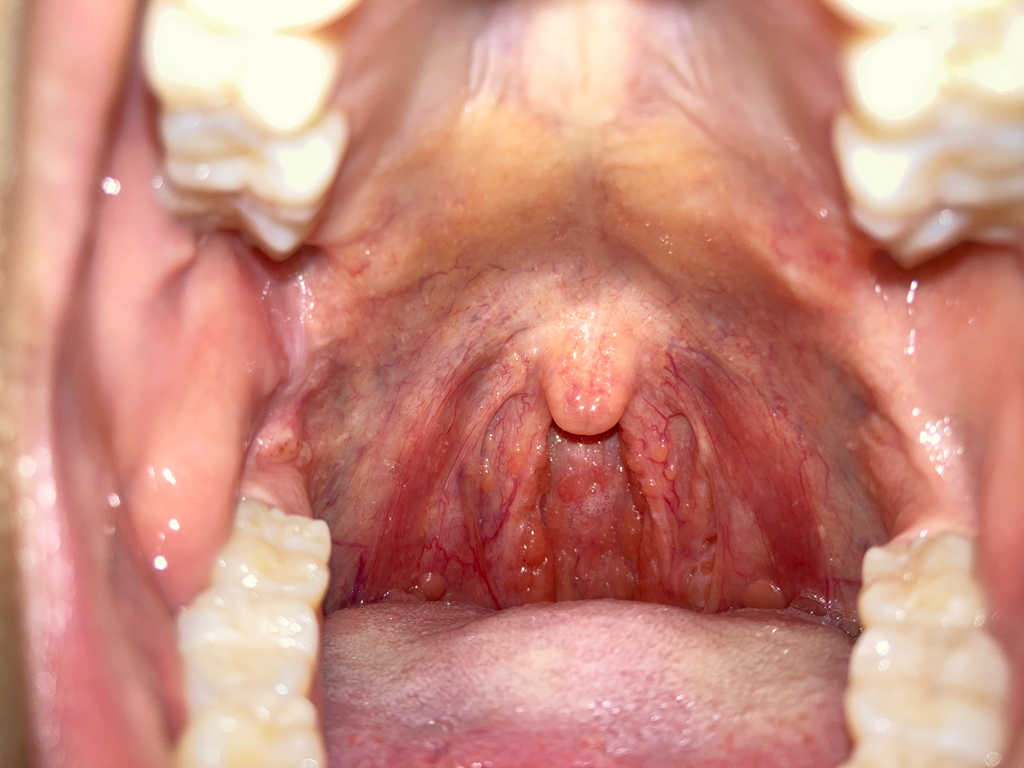

사랑니 근처이고, 씹히는 부분 근처인데 직접적으로 씹히진 않아요 혹 위로 빨갛게 피가 고인 것처럼 보이고 뒤에 하얀 점(구내염 같은)이 있어요... 구내암은 아니겠죠 20대 초반입니다 너무 불안해요

• 1번 째 사진

아마도 구내염으로 추정되는 병변입니다. 구강암의 양상과는 차이가 있으니 안심하시고 이비인후과 내원하셔서 적절한 치료를 받는 것을 권유드립니다.